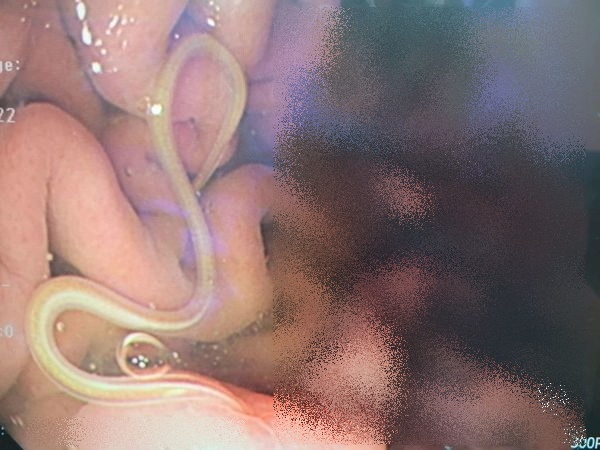

Quả nhiên, kết quả nội soi cho thấy dự đoán của bác sĩ Vũ là hoàn toàn chính xác. Bệnh nhân cũng phải hoảng hốt khi tận mắt nhìn thấy những con giun Anisakis sống đang làm tổ trong bụng mình. Chúng liên tục di chuyển trong dạ dày và tấn công thành ruột, cố gắng chui vào các mạch máu.

Hình ảnh nội soi ký sinh trùng Anisakis tấn công thành ruột của bệnh nhân (Ảnh bác sĩ cung cấp)

Loại ký sinh trùng này rất dễ xuất hiện trong hải sản tươi sống hoặc nấu chưa chín kỹ. Thường dài 1 - 2cm và cuộn tròn trong thớ thịt nên khá khó phát hiện bằng mắt thường. Trong khi món sashimi bệnh nhân ăn hoàn toàn là hải sản tươi sống. Khi xâm nhập vào cơ thể người, Anisakiasis gây nhiễm trùng, dẫn đến đau bụng dữ dội, buồn nôn và nôn mửa. Khi chui vào thành ruột, chúng có thể gây ra phản ứng miễn dịch cục bộ hoặc viêm trong ruột rất nguy hiểm.